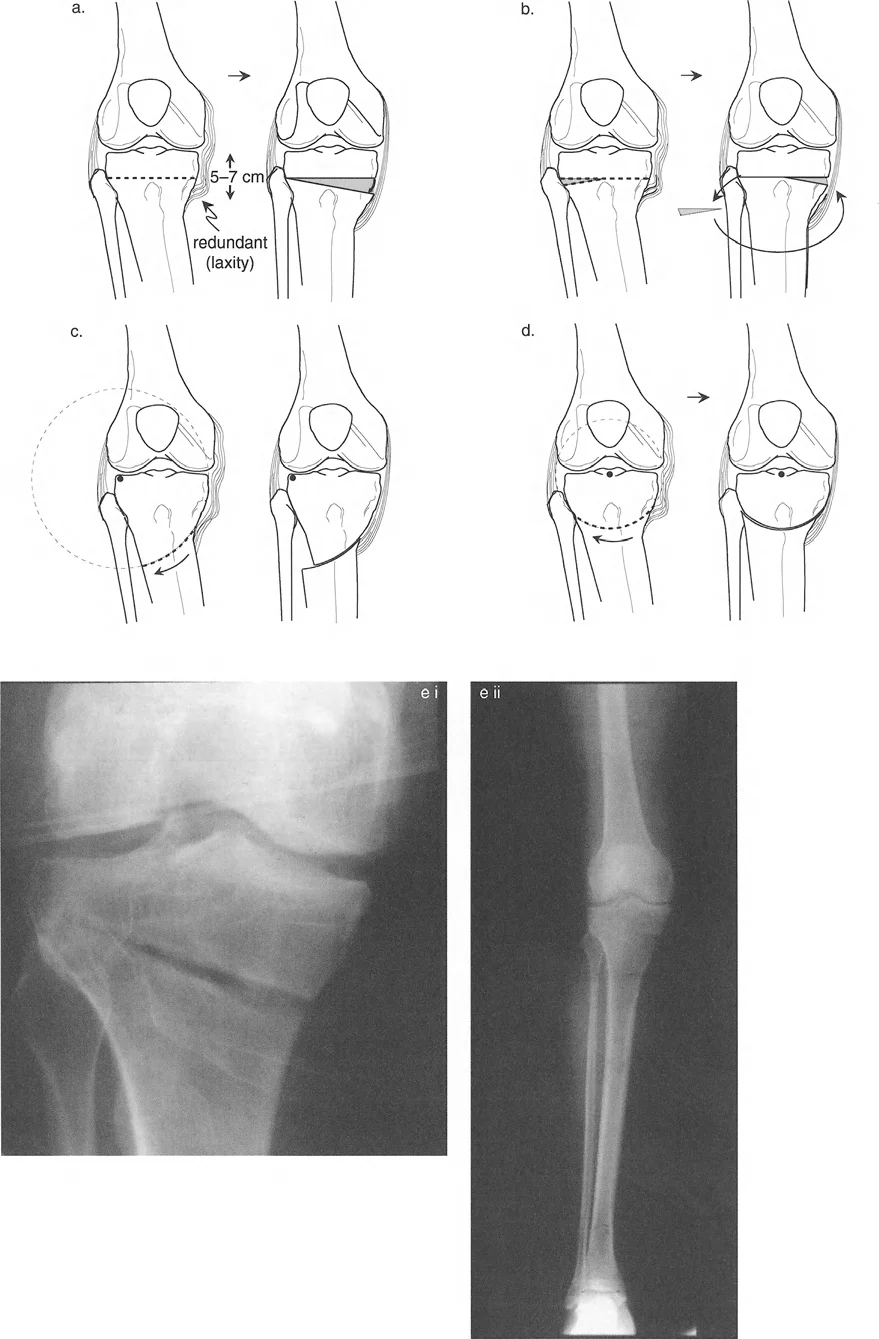

التشخيص الدقيق لمشكلات المحاذاة وتطبيق مبادئ بالي

يُعد التشخيص الدقيق هو حجر الزاوية في علاج تشوهات الأطراف السفلية. بدون فهم واضح لمصدر التشوه وتأثيره على الميكانيكا الحيوية للمفصل، لا يمكن التخطيط لعلاج فعال. هنا تبرز أهمية مبادئ بالي (Paley's Principles) التي وضعها الدكتور درور بالي، والتي تُعد معيارًا ذهبيًا في تقييم وتصحيح تشوهات الأطراف السفلية.

مبادئ بالي لاتجاه المفصل (Paley's Principles of Joint Orientation)

بعد تحديد محاذاة الطرف السفلي (MAD)، يجب على الجراح تقييم اتجاه المفاصل بشكل منهجي بالنسبة للمحور الميكانيكي. لكل مفصل ميل طبيعي يمكن التنبؤ به بدرجة عالية. تشكل هذه القيم الطبيعية الخطوط والزوايا المرجعية التي تُعد متطلبات أساسية للتخطيط قبل الجراحة ولتحديد مركز دوران الزاوية (CORA).

الهدف النهائي لأي جراحة لتصحيح التشوه هو هدفان:

- استعادة المحاذاة الخطية الطبيعية: القضاء على MAD بحيث يمر المحور الميكانيكي عبر مركز الركبة.

- استعادة اتجاه المفصل الطبيعي: التأكد من أن خط المفصل لكل مفصل يقع بزاوية صحيحة بالنسبة للمحور الميكانيكي، مما يمنع قوى القص التي تدمر الغضروف.

مساهمات باولز وماكيت (Pauwels and Maquet): رواد الميكانيكا الحيوية

كان فريدريش باولز (Friedrich Pauwels) في الثمانينيات من أوائل الجراحين الذين أدركوا الأهمية العميقة للميكانيكا الحيوية وعلاقتها المباشرة بالتخطيط الجراحي لتصحيح التشوه عبر قطع العظم. لقد أ